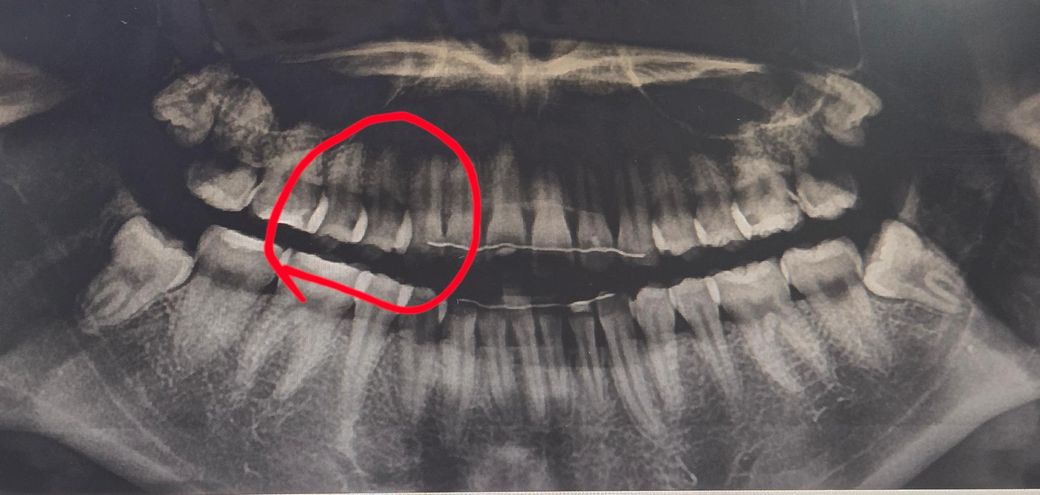

인접면 충치 봐주세요..!!치료가 필요한 정도인지 궁금합니다

지금은 레진 4개하고 왼쪽 어금니 끝에서 두번째꺼 양옆으로 썩은 인접면 충치 치료까지 완료한 상탠데 한 치과에서는 저부위의 인접면충치를 언급하지 않았고 한치과에서는 아직 법랑질 내에 있는걸로 보이나 인접면충치가 있다고 하셨습니다

확실히 충치가 있는갈까요? 그리고 인접면의 걍우 인레이라 식제량이 많이서 최대한 피하고 싶은데 일단 관리하면서 지켜봐도될까요?

파노라마 사진상으로는 충치가 잇어 보입니다. 정확한 진단을 위해서는 작은 사진을 찍어보시는게 좋을것같습니다.

사진으로 봤을 경우에는 인접면의 충치가 있는 것으로 보입니다. 하지만 사진으로만은 정확한 확인이 어렵습니다. 정확한 확인을 위해서는 육안으로 확인을 할 필요가 있을 것으로 생각됩니다.

인접치아끼리 겹치는 파노라마 사진은 인접면 충치 정도 판단하는데 별 의미가 없고 부정확합니다. 치근단 사진을 찍어봐야 합니다. 파노사진으로는 어디에 충치가 있다 없다 정도를 말할 수 있을 것 같습니다. 위 사진에서 동그라미 표시된 부위 말고 그 반대쪽 어금니 인접면 충치도 있는 것으로 보여서 치근단 사진으로 충치 정도를 확인해봐야 할 것 같습니다.